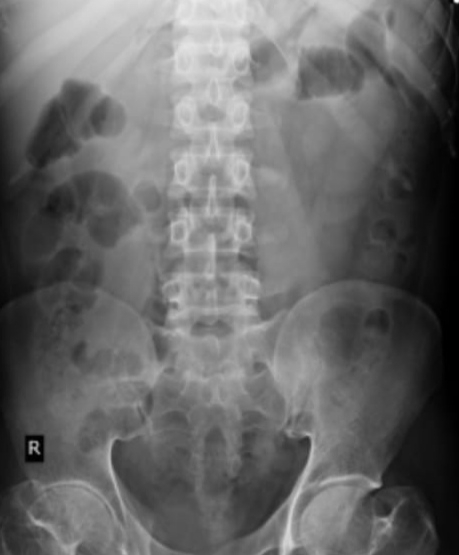

Acute urinary retention under evaluation,? Potts spine.

On USG ABDOMEN AND KUB : No sonological abnormalities detected

Urology referral taken for decreased urine output, adviced for Urine AFB, NCCT KUB, Urine C/S, gramstain,AFB

Urology opinion taken agian after the NCCT , culture reports, and USG

USG done and it says normal prostrate size with normal bladder wall thickening

NCCT is normal